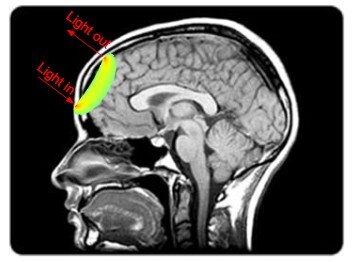

Inside Open-MOTION: How We’re Using Light to Detect Stroke in Minutes

The third post in our series exploring Openwater’s vision, technology, and community.